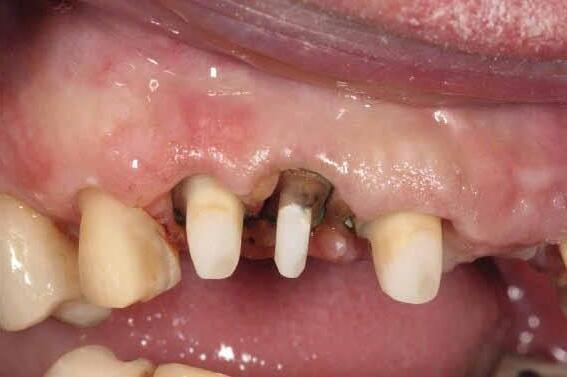

Fig 14. Clinical view at two days post-operative visit.

Fig 15. Clinical view at two days post-operative visit

Fig 16. Patient’s smile after implantation and previsualization